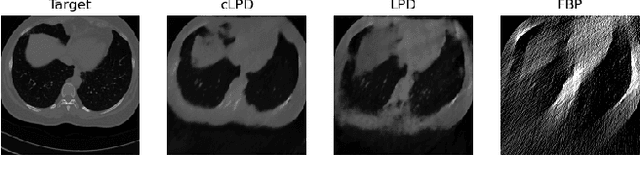

Neural ordinary differential equations (Neural ODEs) propose the idea that a sequence of layers in a neural network is just a discretisation of an ODE, and thus can instead be directly modelled by a parameterised ODE. This idea has had resounding success in the deep learning literature, with direct or indirect influence in many state of the art ideas, such as diffusion models or time dependant models. Recently, a continuous version of the U-net architecture has been proposed, showing increased performance over its discrete counterpart in many imaging applications and wrapped with theoretical guarantees around its performance and robustness. In this work, we explore the use of Neural ODEs for learned inverse problems, in particular with the well-known Learned Primal Dual algorithm, and apply it to computed tomography (CT) reconstruction.